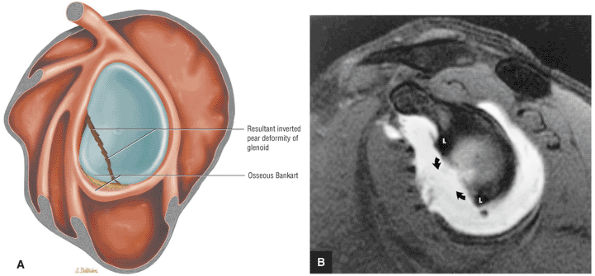

identified. In patients with a history of recurrent dislocations, a sagittal image through the glenoid demonstrates deficiency of the anterior inferior glenoid, manifested as bony Bankart fractures through the anterior inferior glenoid or remodeling and attrition of the anterior inferior glenoid, resulting in an “inverted pear” appearance. Subchondral cystic changes in the glenoid are seen as focal high-signal areas within the glenoid, suggesting overlying chondromalacia.

FIGURE 8.30 ● Axial images through the AC joint should be obtained on all shoulder MR examinations. (A) Axial T1- or PD-weighted images at this location are used to identify fractures of the distal clavicle and to demonstrate an os acromiale. (B) Axial FS PD-weighted images show cartilage covering the distal aspect of the clavicle and the medial aspect of the acromion at the AC joint. Cartilage defects and thinning, as well as subchondral bone marrow edema and cystic change, are evaluated on axial images through the AC joint. These degenerative changes can mimic the symptoms of a rotator cuff tear. (C) Axial T1- or PD-weighted images demonstrate the Hill-Sachs lesion of the humeral head, usually visualized as focal flattening or concave deformities in the posterolateral humeral head. The Hill-Sachs lesions is identified on the first or second superior axial image through the humeral head. Subcortical cystic change is more commonly visualized in the posterolateral humeral head and is usually an incidental finding in asymptomatic patients. (D) Axial FS PD-weighted images depict the biceps tendon coursing across the anteromedial aspect of the humeral head, within the rotator interval. This image location serves as a starting point for following the remainder of the biceps tendon into the bicipital groove on successive axial images moving from cranial to caudal. Tears of the supraspinatus and infraspinatus tendons are also identified at this image location on axial images. (E) Axial T1- or PD-weighted images allow evaluation of subcoracoid impingement. (F) In this location, thickening and increased signal in the superior glenohumeral ligament and coracohumeral ligament on an axial FS PD-weighted image may indicate adhesive capsulitis, particularly when accompanied by thickening and increased signal within the inferior glenohumeral ligament. (G) Axial T1- or PD-weighted images are used to identify subcortical cystic change in the greater and lesser tuberosity. This finding is commonly an indirect indication of abnormality or tearing in the overlying distal supraspinatus and subscapularis tendons, respectively. (H) Axial FS PD-weighted images through the proximal bicipital groove are used to identify “hidden lesions,” which are diagnosed when the biceps tendon is medially subluxing out of the bicipital groove, usually into a distal subscapularis tear or anterior to the lesser tuberosity. A degenerated biceps tendon may appear flattened and elongated as it rounds the lesser tuberosity into the proximal bicipital groove. Commonly, only the medial “tail” of the flattened degenerated biceps tendon subluxes out of the groove; the remainder of the flattened biceps tendon stays within the groove. (I) Axial T1- or PD-weighted images display the osseous glenoid subchondral surface, which should appear flat. Osseous glenoid remodeling, hypertrophy, deformity, subchondral cystic change, and edema are commonly identified as indirect evidence of overlying chronic cartilage degeneration or prior trauma. Posterior glenoid spurring may completely replace a degenerated or markedly attenuated posterior labrum. (J) Axial FS PD-weighted images are optimal for displaying the glenoid and humeral head cartilage. Chondral fissures, thinning, and defects are visualized when viewing successive cranial-to-caudal images through the glenohumeral joint. The anterior and posterior labrum are also optimally visualized and are normally firmly adherent to the glenoid and glenoid articular cartilage. (K) Axial T1- or PD-weighted images are used to identify bony Bankart lesions. These lesions are seen on inferior axial images through the glenohumeral ligament as oblique fracture lines extending through the anterior inferior glenoid. (L) Axial FS PD-weighted images show the prominent anterior band of the IGHL, which is occasionally mistaken for a tear of the anterior inferior labrum when fluid is interposed between the anterior band and the normal labrum.